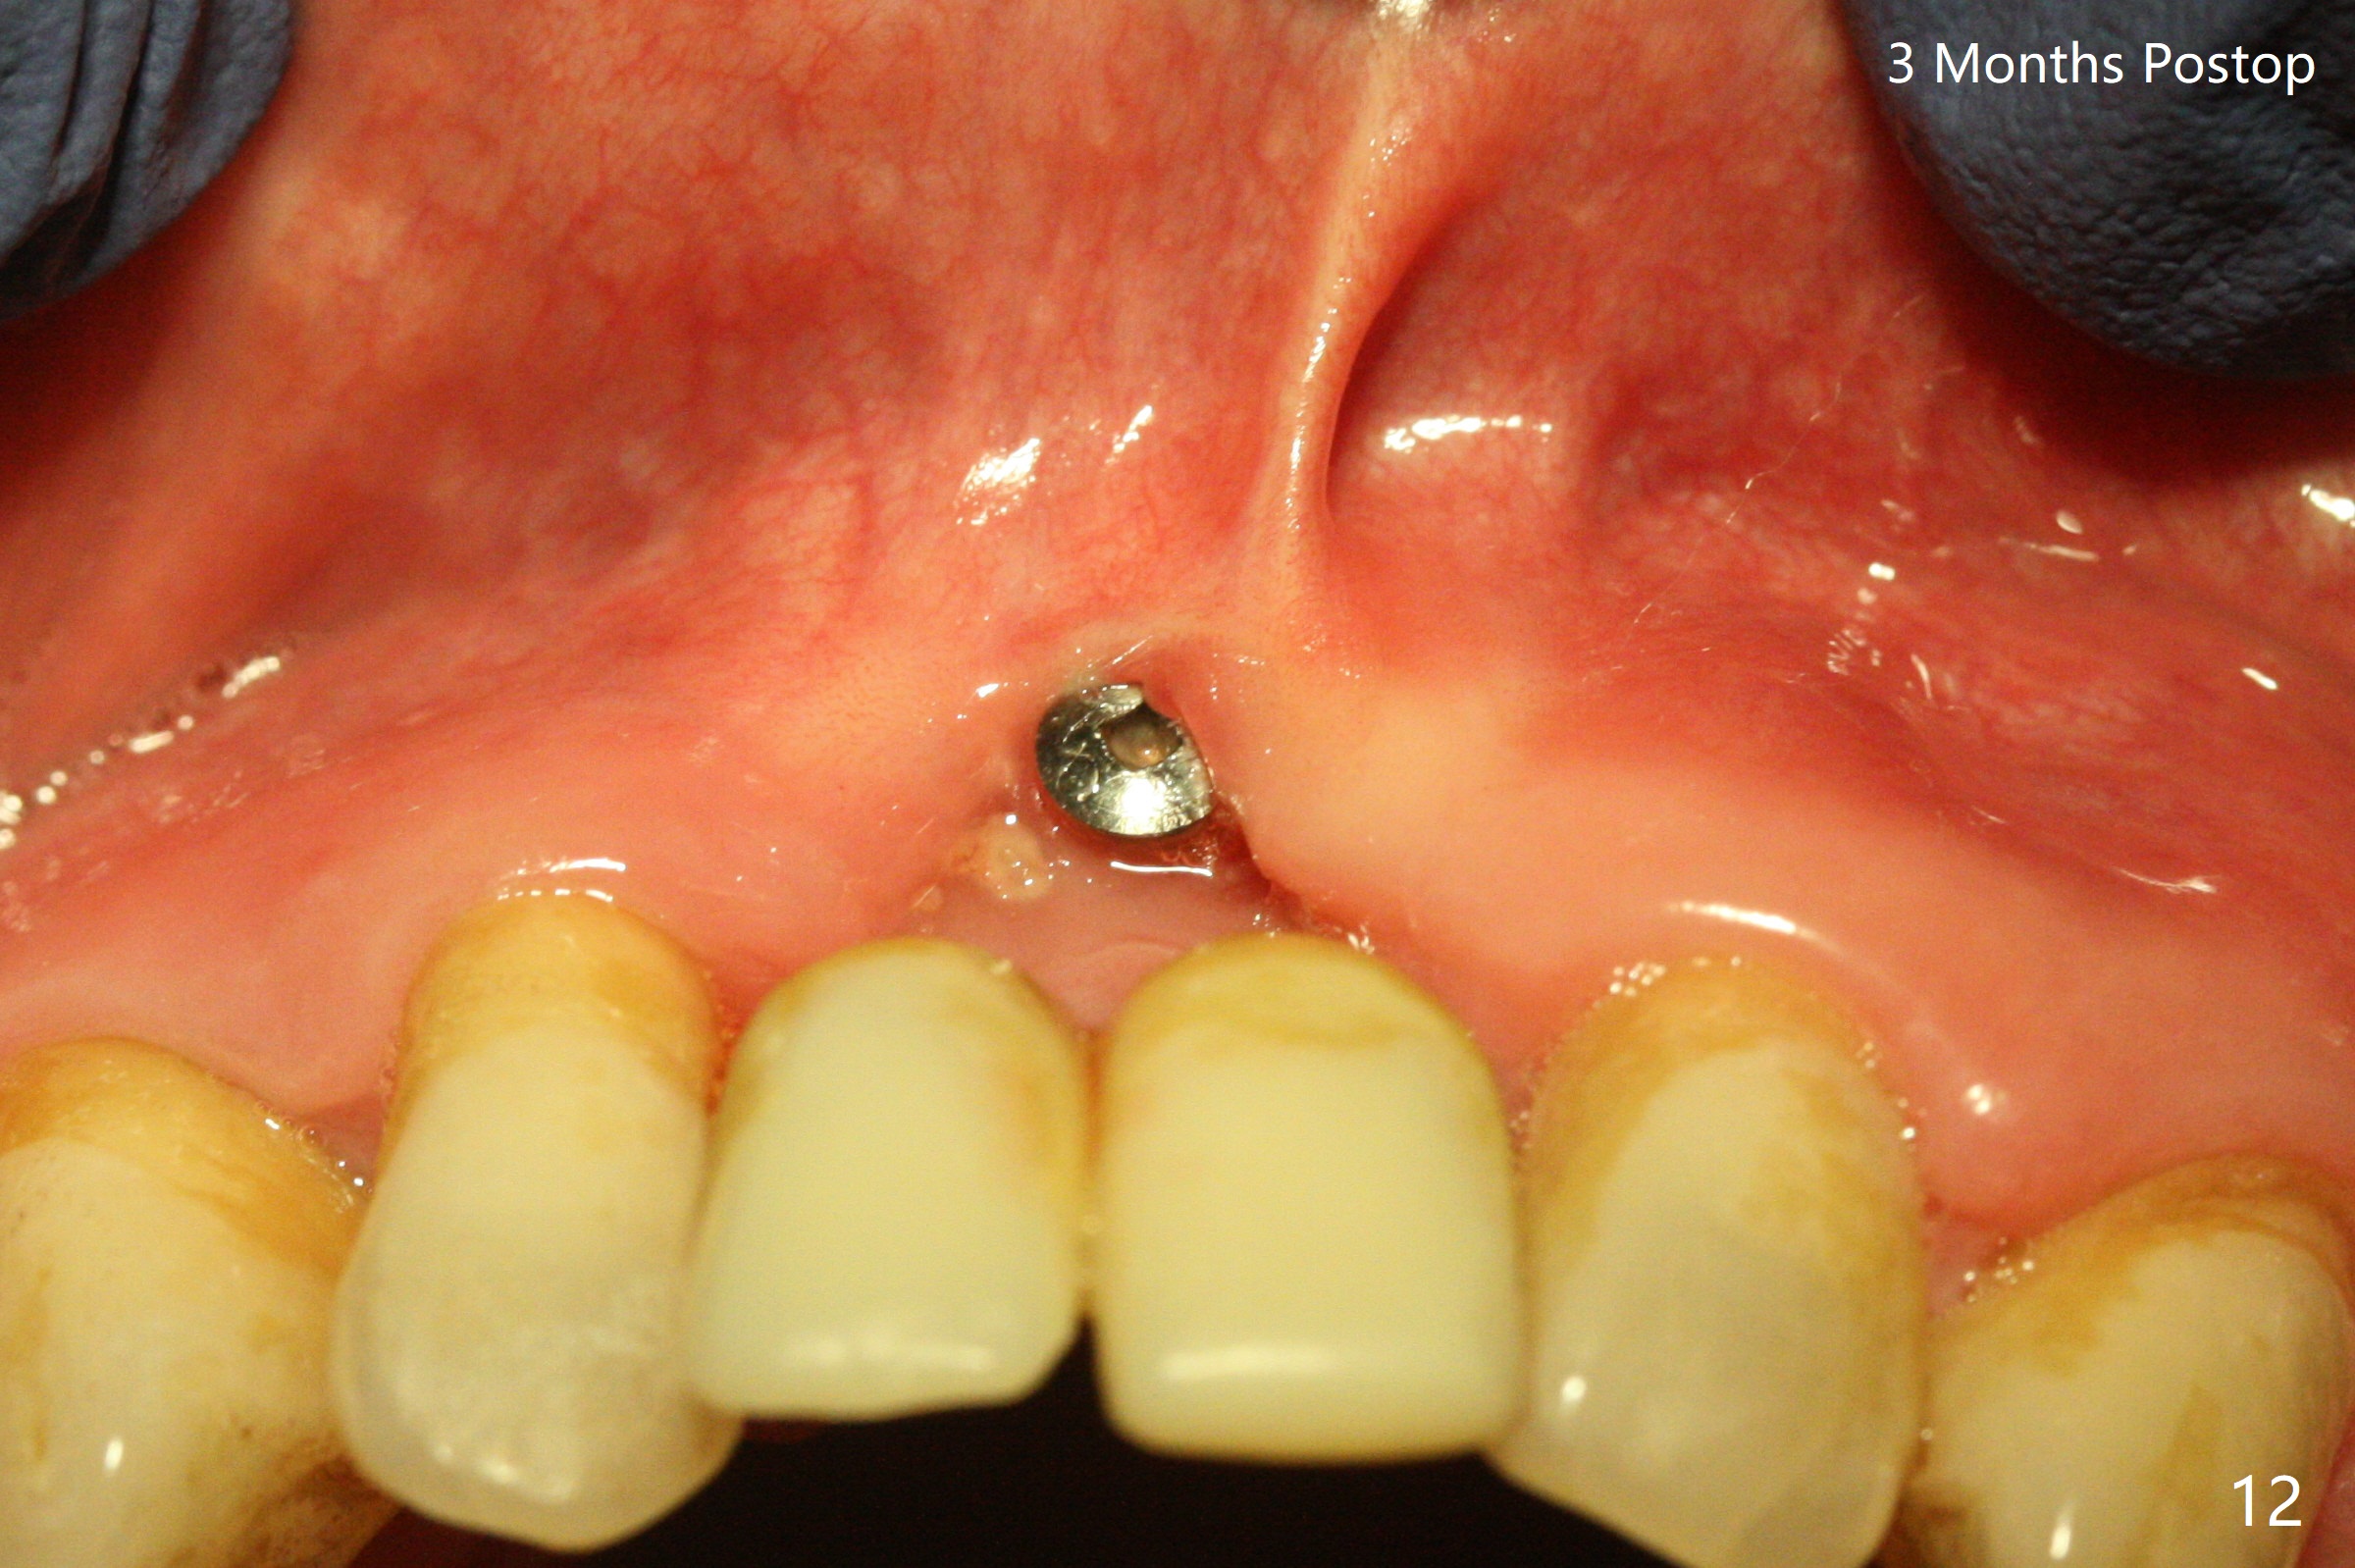

The gingiva remains recessive at #8 and 9 six months post immediate implant placement with bone graft (Fig.1). The buccal plate at #8 is particularly concave before (Fig.2 *) and after (Fig.3) abutment removal. The bony defect repair is assisted by placing a 4 mm tenting screw between the 2 implants (Fig.4) and placing allograft mixed with PRF (as putty) around the screw (Fig.5 (after replacement of the abutments)). The buccal contour improves because of the tenting screw and the bone graft placement (Fig.6 (as well as PRF and 6-month membranes)). The wound dehisces 12 days postop and immediately before leaving country for months (Fig.7). The sutures are removed, Osteogen plug is inserted (Fig.8) and periodontal dressing is applied (Fig.9). PA is taken to show the tenting screw (Fig.10 T). The latter is exposed 3 months postop (Fig.11,12). It appears that gingival graft is a must (Fig.13). Make a palatal stent, remove the temp with abutments and create a bleeding surface before harvesting a large piece of tissue. Connective tissue graft is done 5 months post bone graft (Fig.14). In fact there is no implant thread exposure. In fact the connective tissue graft does not survive. The abutments are re-prepared for pink porcelain (Fig.15). The bone loss is stable 1 year post cementation in spite of incomplete abutment seating (Fig.16). The soft tissue is nearly normal (Fig.17).